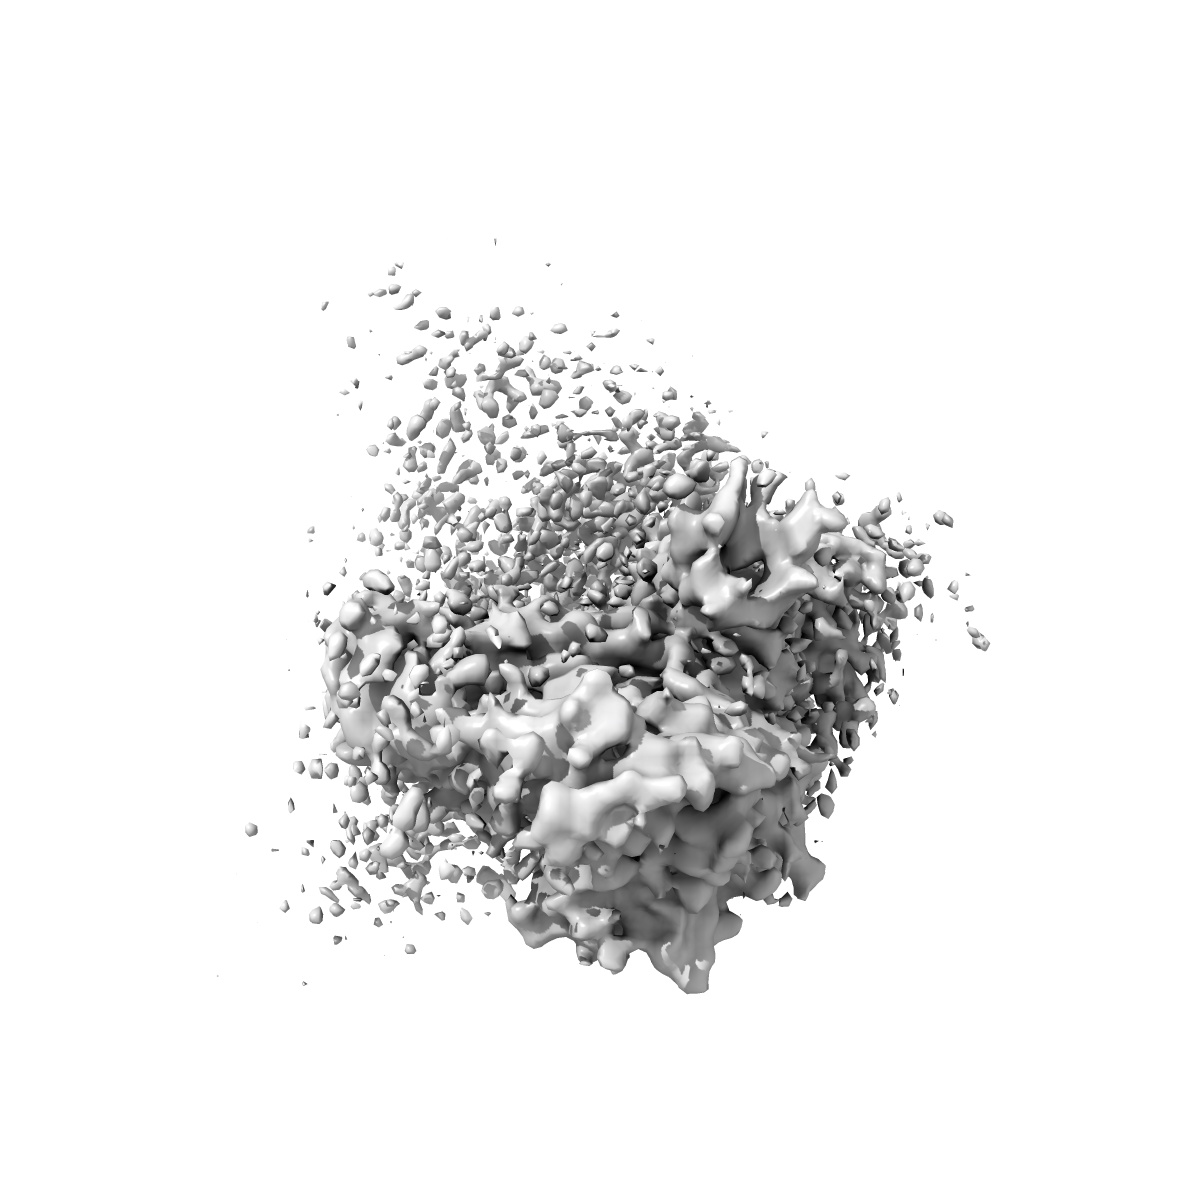

Local CryoEM structure of the SARS-CoV-2 BA.5 in complex with ORB10 Fab

Single-particle3.6 Å

Sample: SARS-CoV-2 BA.5 Spike in complex with ORB10 Fab